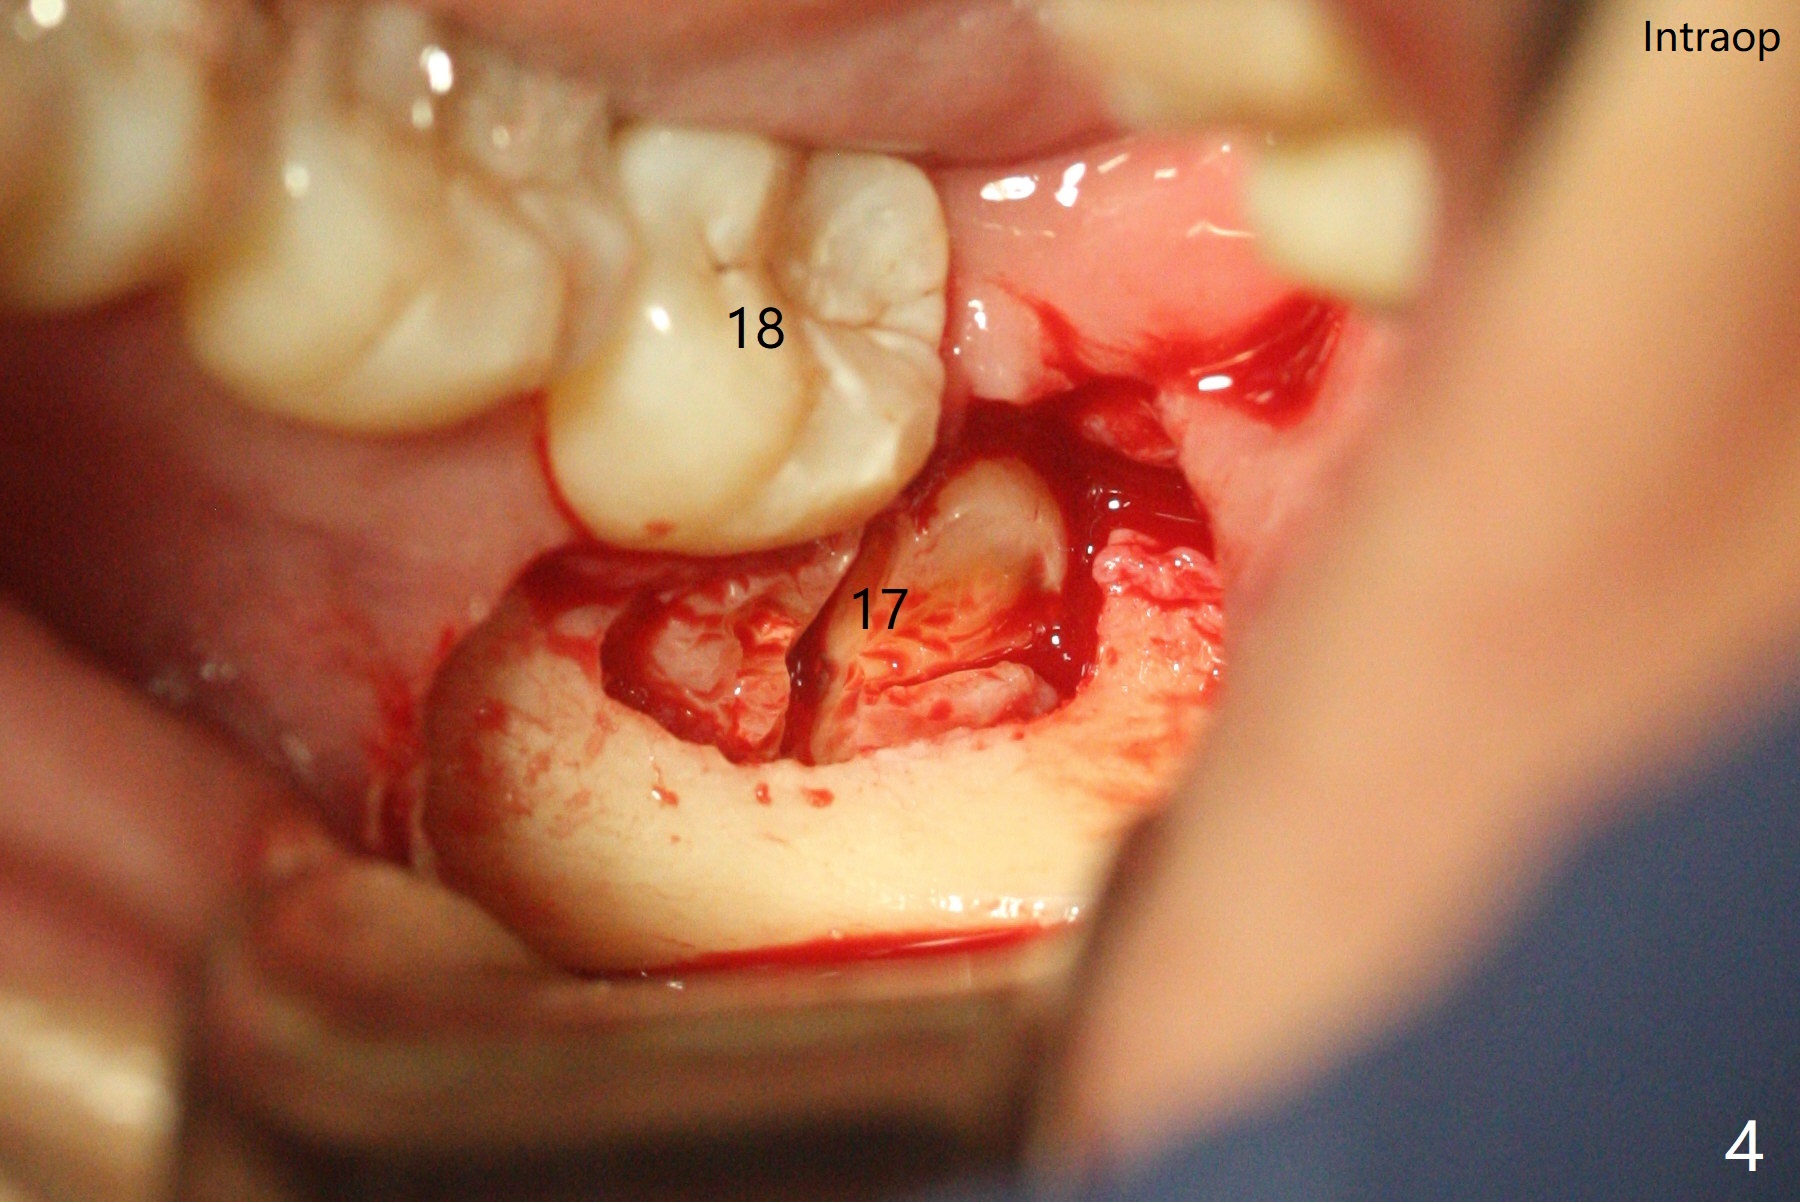

A 35-year-old timid woman finally decides to have 4 of the 3rd molars extracted (Fig.1). The apices of #17 overlaps with the Inferior Alveolar Canal (*). Small field CT shows that #17 is buccal to #18 (Fig.2), causing distal root exposure (Fig.3 D). In fact the buccal overlap seems to be more severe clinically (Fig.4) than what X-ray indicate (Fig.1,3). Therefore bone graft seems to be able to be packed mesially (Fig.5: G). In fact the left Inferior Alveolar Canal is exposed after extraction, collagen plug (P) is placed distal without use of curette around the exposed canal.